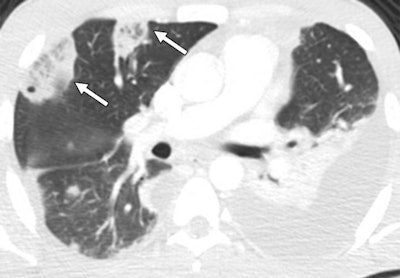

Chest CT scan showing two reversed halo signs (arrows) with central reticulation in the anterior segment of the right upper lobe. Image courtesy of AJR.Almeida and colleagues found that the reversed halo sign had a statistically significant association with septic PE in IV drug users (Cohen's kappa coefficient range, 0.84 to 0.96; p < 0.0001). They also found an average of two reversed halo signs per patient.